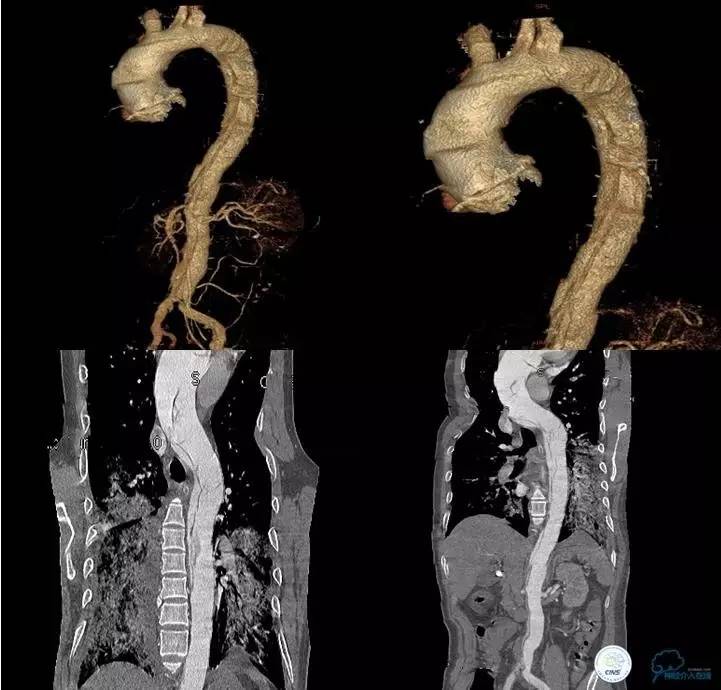

▼主动脉全程CT

诊断:

主动脉夹层 DeBakey Ⅰ型

短暂性脑缺血发作

急性心肌缺血

急性肾功能不全

急性肠系膜动脉缺血

中间诊断:

主动脉夹层 De Bakey Ⅰ型

脑梗死

治疗原则:

继续监测血流动力学指标

绝对卧床、控制血压、强效镇静与镇痛

急请血管外科会诊